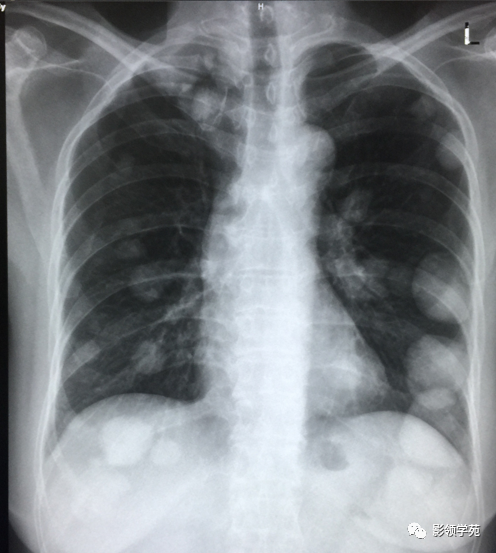

肺转移瘤。肺窗像(A)示双肺野可见大小不等的圆形高密度结节影,纵隔增宽;纵隔窗像(B)示肺内肿块呈实性,纵隔满布大小不等的肿大淋巴结

CT诊断:甲状腺癌双肺多发转移